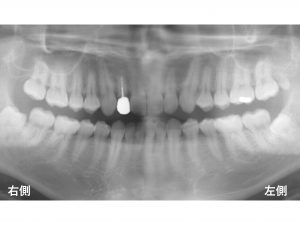

以下が初診時です。

上顎の前歯がグラグラする

とのことで来院されました。

以下は、治療後です。